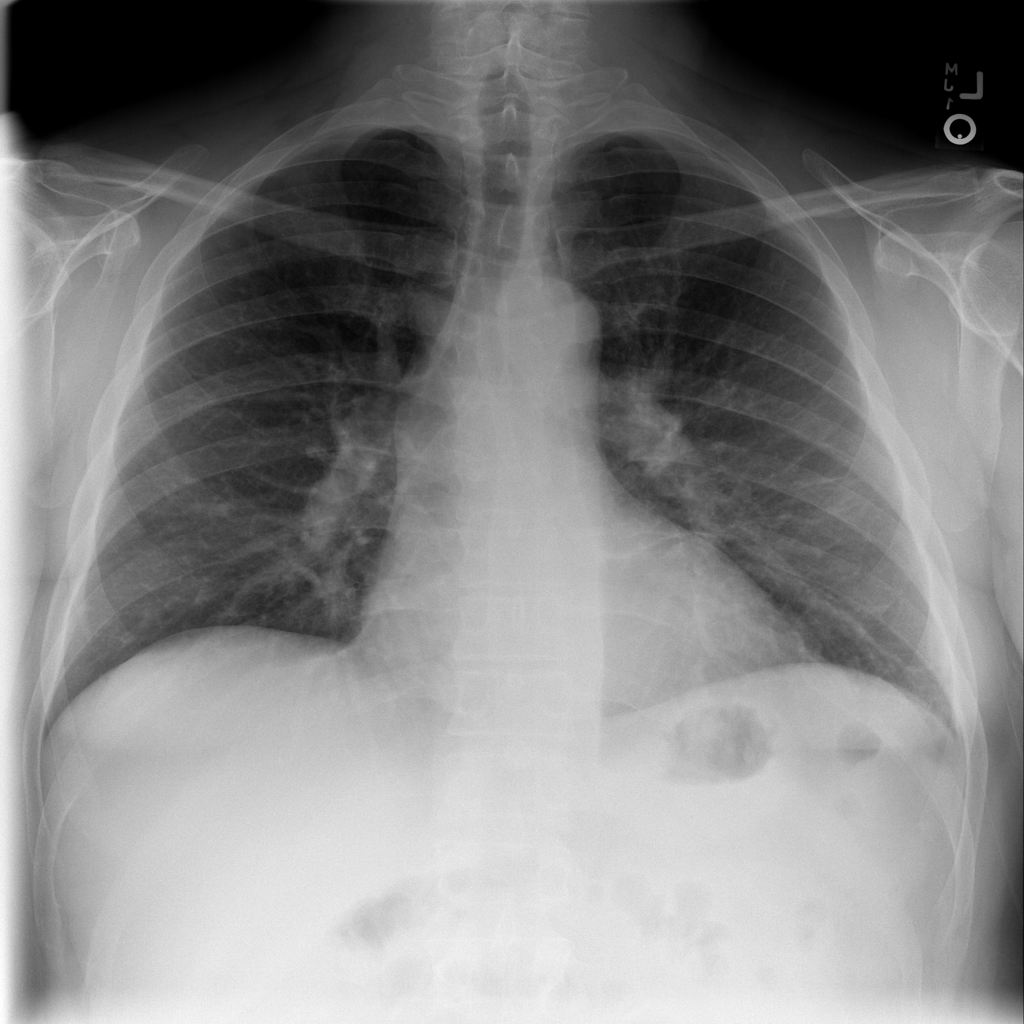

PAT-06B1 · IMG-023Fibrosis

PAT-06B1 · IMG-023

AP